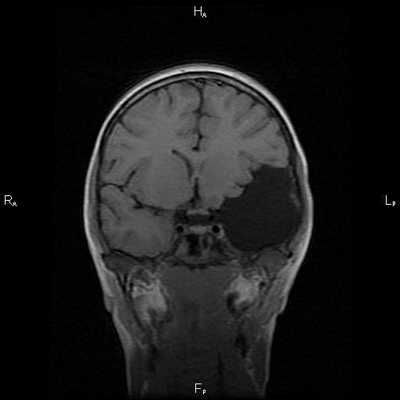

Арахноидальные кисты представляют собой скопление ликвора между листками расщепленной паутинной оболочки. Арахноидальная киста обычно не сопровождается другими мальформациями. Незначительная часть арахноидальных кист имеет приобретенное происхождение - следствие лептоменингита, операции или кровоизлияния. Частота составляет около 1% от внутричерепных образований. Соотношение полов М:Ж, как 4:1. Типичная локализация - средняя черепная ямка (в области Сильвиевой борозды 50%), межполушарная щель, мосто-мозжечковый угол (11%), за скатом или на уровне четверохолмия (10%), в области червя мозжечка (9%), реже в области межножковой и предмостовой цистерн (3%), а также супраселлярной и хиазмальной цистерн. В зависимости от размера предложено делить кисты на 3 типа (Galassi, 2006), что однако, не имеет практического значения. Ретроцеребеллярная арахноидальная киста довольно часто встречаются за мозжечком и отличима от mega cisterna только по неизменённой задней черепной ямке. При МРТ головного мозга содержимое кисты чисто ликворное, стенки гладкие, чётко очерченные, внутри кисты могут быть перегородки. Мелкие арахноидальные кисты очень трудно увидеть при МРТ головного мозга. Меняя ширину окна и его уровень на Т1-зависимых МРТ изображениях можно заметить, что киста чуть светлее ликвора. Дифференциальная диагностика с эпидермальными кистами лучше осуществляется с помощью МРТ последовательности FLAIR. На них при МРТ головного мозга эпидермальные кисты становятся яркими, в отличие от гипоинтенсивных арахноидальных. Вероятно, вариантом арахноидальной кисты является нейроэпителиальная киста, которая при МРТ головного мозга имеет типичное расположение в области хориоидальной щели.